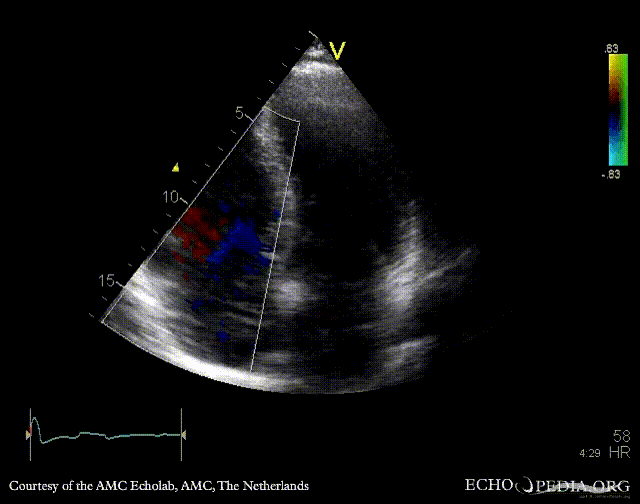

Chiari network

A4CH: Color Doppler